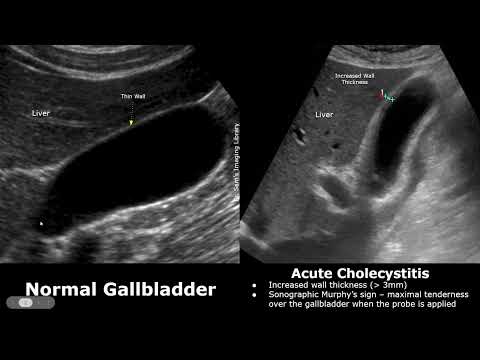

Image of Gallbladder Ultrasound Normal Vs Acute Cholecystitis

Gallbladder Ultrasound Normal Vs Acute Cholecystitis | Gallstones Sludge Thickened GB Wall USG